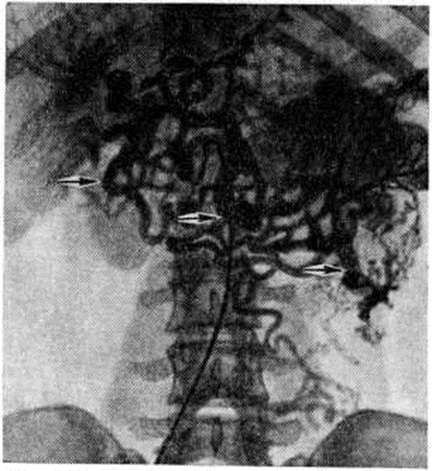

Нередко первым симптомом, выявляющим заболевание (особенно при внепечёночной форме Портальная гипертензия), является случайно обнаруженная увеличенная селезёнка или внезапно возникшее кровотечение из вен пищевода. Больные жалуются на общее недомогание, чувство тяжести в левом подреберье, иногда сопровождающееся болями и повышением температуры, метеоризм, увеличение живота. У больных с асцитом часто выявляются расширенные вены на передней брюшной стенке вокруг пупка (голова медузы) либо по направлению к грудной клетке или надлобковой области (рисунок 2) с характерным при аускультации шумом волчка над ними. Портокавальные анастомозы возникают при внутрипечёночном блоке портальной системы в результате функционирования пупочной вены и обозначаются как синдром Крювелье — Баумгартена (смотри полный свод знаний: Крювелье — Баумгартена синдром). При болезни Киари расширенные вены локализуются чаще по боковым стенкам живота (рисунок 3), на спине и нижних конечностях.

Рис. 3. | ||

Наибольшую информативность об уровне блокады портального кровообращения и состоянии сосудов даёт спленопортография. При внутрипечёночной Портальная гипертензия спленопортальное русло проходимо, расширено с резким обеднением сосудистого рисунка печени, иногда выявляются расширенные вены желудка и пищевода, расширенная пупочная вена (рисунок 4). При внепечёночной Портальная гипертензия отмечается разнообразная картина в зависимости от уровня блокады (рисунок 5), вплоть до полной непроходимости спленопортального русла. В этом случае для установления уровня блокады применяют возвратную мезентерикопортографию (рисунок 6). При надпечёночной Портальная гипертензия наибольшую информацию даёт кавография и пункционная биопсия печени. Расширенные вены пищевода и желудка, как правило, выявляются при их рентгенологическом или эндоскопическом исследовании.